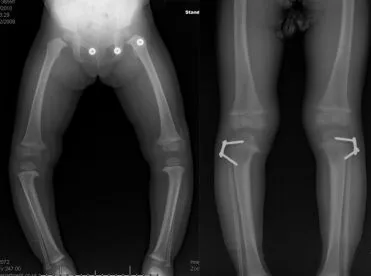

记录波兰女孩安娜在 Paley 研究院治疗先天性胫骨假关节(CPT)并合并 NF1 的完整过程:诊断、Ilizarov 外固定器手术、延长与矫正、长期随访与康复,展现专业治疗与家庭陪伴带来的可复制希望。